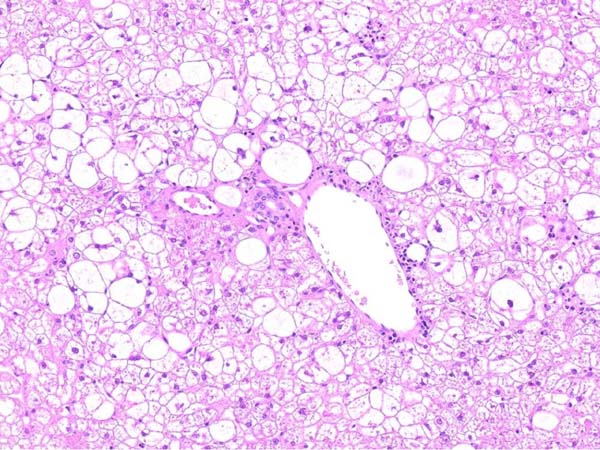

ワンちゃんが乳腺にできた複数のシコリを気にされて来院されました。bilateral mastectomyで対応しました。摘出後の病理組織検査の結果は、「R3-4間腫瘤:乳腺癌(複合型)」でそれ以外は「良性乳腺混合腫瘍」でした。無事元気に退院し、その後再発もなく経過は良好です。よかったね。